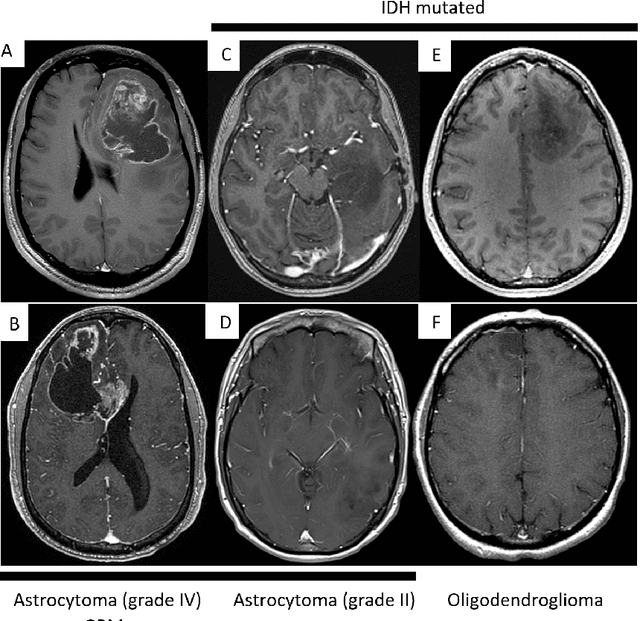

Abstract:Primary brain tumors including gliomas continue to pose significant management challenges to clinicians. While the presentation, the pathology, and the clinical course of these lesions is variable, the initial investigations are usually similar. Patients who are suspected to have a brain tumor will be assessed with computed tomography (CT) and magnetic resonance imaging (MRI). The imaging findings are used by neurosurgeons to determine the feasibility of surgical resection and plan such an undertaking. Imaging studies are also an indispensable tool in tracking tumor progression or its response to treatment. As these imaging studies are non-invasive, relatively cheap and accessible to patients, there have been many efforts over the past two decades to increase the amount of clinically-relevant information that can be extracted from brain imaging. Most recently, artificial intelligence (AI) techniques have been employed to segment and characterize brain tumors, as well as to detect progression or treatment-response. However, the clinical utility of such endeavours remains limited due to challenges in data collection and annotation, model training, and in the reliability of AI-generated information. We provide a review of recent advances in addressing the above challenges. First, to overcome the challenge of data paucity, different image imputation and synthesis techniques along with annotation collection efforts are summarized. Next, various training strategies are presented to meet multiple desiderata, such as model performance, generalization ability, data privacy protection, and learning with sparse annotations. Finally, standardized performance evaluation and model interpretability methods have been reviewed. We believe that these technical approaches will facilitate the development of a fully-functional AI tool in the clinical care of patients with gliomas.